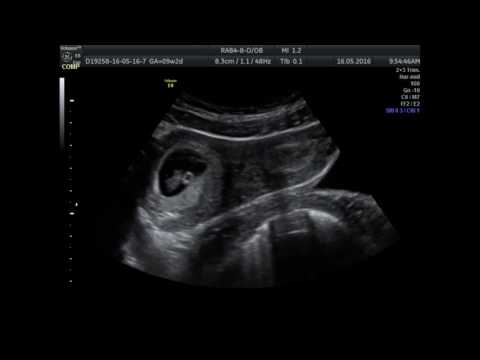

Ультразвуковое исследование органов малого таза (УЗИ)

Данный метод, к сожалению, не всегда помогает обнаружить седловидную матку.

Подчеркнем, что при данном методе диагностики обращают внимание на высоту эндометрия и ширину матки. Многими проведенными экспериментами доказано, что это 2 наиболее важных критерия, которые могут подтолкнуть врача ультразвуковой диагностики к данному диагнозу.

Итак, толщина эндометрия (М-эхо) при седловидной матке составляет больше 2.16 мм во второй фазе менструального цикла. Ширина же матки при ее седловидности увеличивается до 68 мм. Этот метод хорош тем, что он абсолютно не оказывает дискомфорта женщине, тем более он является наиболее доступным для всех женщин.